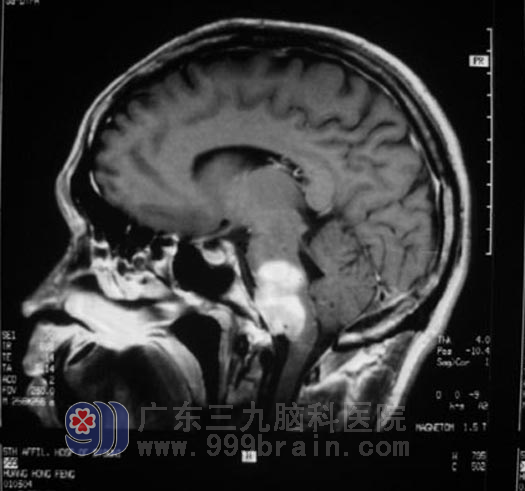

黄先生,31岁,1个月前无明显诱因开始出现双眼视力下降,当时无明显头痛、头晕,无肢体乏力、麻木不适,未予注意。直到双眼视力下降逐渐加重,右侧肢体开始出现乏力、麻木,后枕部疼痛,言语不清,进食呛咳才去了医院。拿着“桥脑、延髓占位,大小约3.7*2cm,强化明显”的MR影像片,在多家医院求医无果后,家人都明白,死神已向黄先生露出狰狞的面容。

在组织放射科、麻醉科等相关学科协同会诊,确立手术方案后,1月5日由鲁明主任主刀,术中见肿瘤明显压迫舌咽神经、迷走神经、副神经及设下神经,小脑后下动脉、椎动脉与肿瘤紧密联系,肿瘤与脑干粘连紧密,手术难度比预想的大多了,显微镜下将肿瘤顺利切除,整个手术持续近6个小时。手术后的黄先生康复很快。

▲手术前